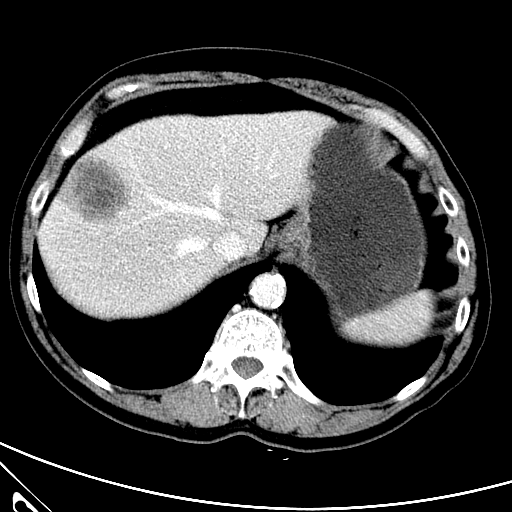

Refer to caption

(a) CT images.

(b) MRI images.

Figure 6: Lossy compression based attack on CT images (a) and MRI images (b) with a specific channel numbers (C8050\mathrm{C^{50}_{80}}) for the EP and IT Scenarios. StolenEPD1\mathrm{Stolen}^{\mathrm{D1}}_{\mathrm{EP}} denotes the decompressed images in the EP Scenario with a reduced D1 decoder.

Compression-Fidelity Compromise. Based on the previous results, we have selected the decoder D1D1 and the configuration of the latent and hyperlatent variables C8050\mathrm{C^{50}_{80}}, as the optimal architecture of the HiFiC encoder-decoder pair. In Fig. 6, we display more specifically the compression and reconstruction quality performances. In terms of reconstruction quality, we obtain a PSNR of approximately 40 for CT images and around 38 for MRI images while the MS_SSIM values are close to 1. This indicates an excellent perceptual quality of the reconstructed images that are hardly discernible from the original ones. In terms of compression efficiency, the Pratio\mathrm{P}_{\mathrm{ratio}} for CT images is approximately 0.015, indicating that the lossy image compression-based attack generated compressed images are 67 times smaller than those produced by the lossless zipped image compression-based attack. For MRI images, the Pratio\mathrm{P}_{\mathrm{ratio}} is around 0.12, 10 times higher than that of CT images, which can be attributed to the presence of a large uniform background in the skull-stripped original MR images.